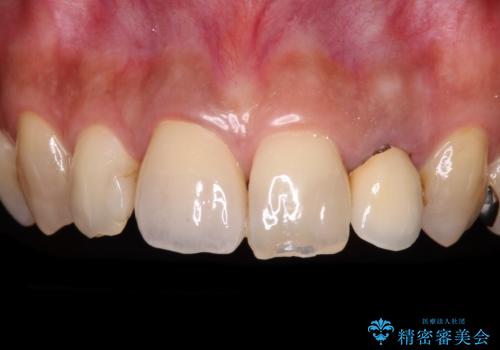

[ 歯が小さい ] 根管治療を伴う矮小歯治療

![[ 歯が小さい ] 根管治療を伴う矮小歯治療の症例 治療前](https://seimitsushinbi.jp/wp/wp-content/uploads/2021/09/c31c85cea60404f69948fd7103e8c7ca-500x350.jpg?v=1632883039)

![[ 歯が小さい ] 根管治療を伴う矮小歯治療の症例 治療後](https://seimitsushinbi.jp/wp/wp-content/uploads/2021/09/80796f663a2a5f8bf47550dede73495e-500x350.jpg?v=1632882140)